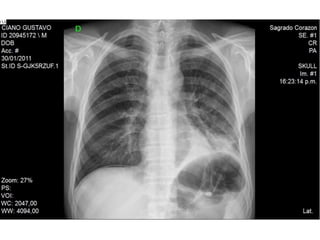

Rx Torax

• Nombre Y Fecha

• Bípeda

• Centrada

• Buena penetración : T4

• Bien Inspirada: Arcos costales anteriores 6-7-

Posteriores 10-11

• Evaluación Radiológica